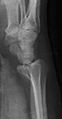

File:Radiograph_of_Barton's_fracture.jpg|Volar Barton's fx | |||

- Fracture-dislocation of distal radius extending into radiocarpal joint

- Two types: volar and dorsal (based on direction of dislocation)

- PA

- Comminuted fracture of distal radial metaphysis

- Lateral

- Intra-articular fracture of volar or dorsal rim of radius